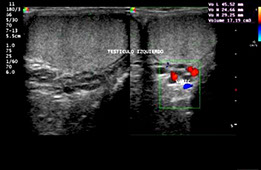

• Ecotomografías Urológicas